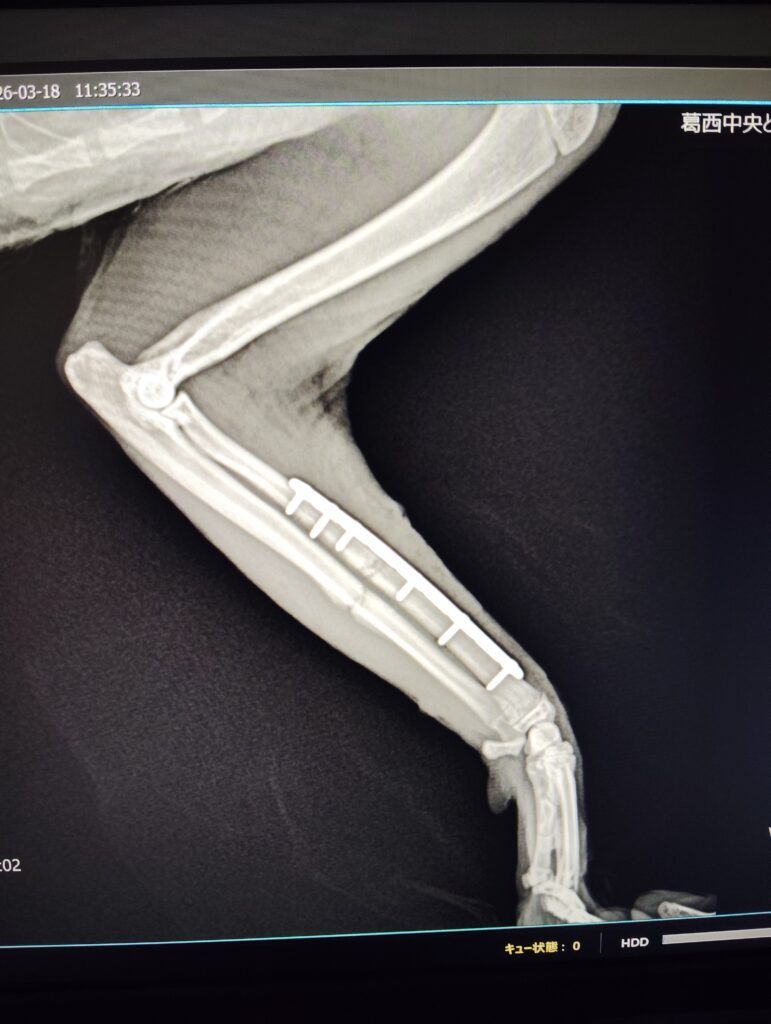

・φ1.5mmのロッキングプレートを使用

術後

3日後圧迫包帯を抜去、早期に着肢を確認